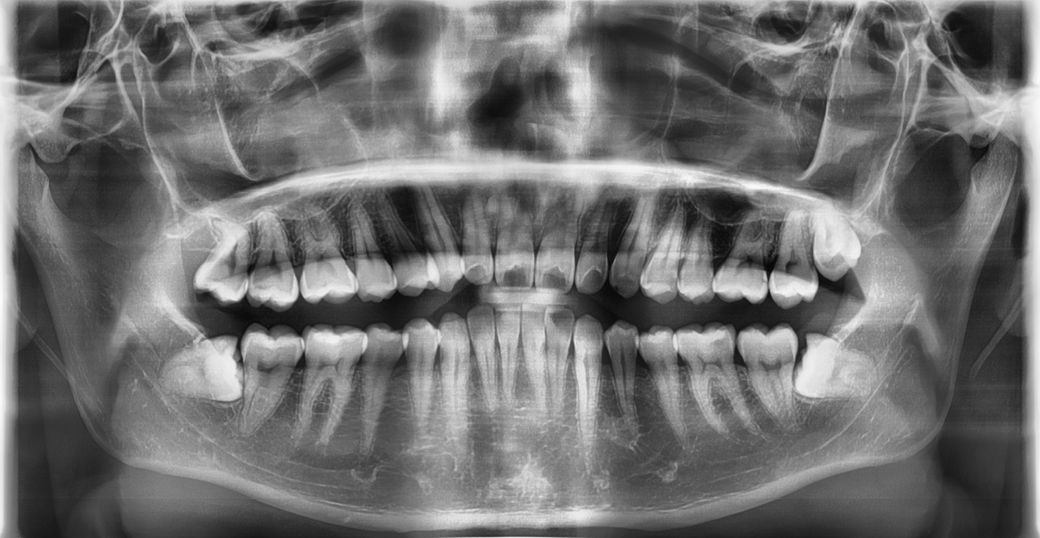

오른쪽 아래 맨 마지막 이에 충치가 있어서 치과에 방문을 했는데 오른쪽 아래 맨 마지막 이는 심하다 하셔서 바로 인레이 치료를 했는데 왼쪽 아래쪽에도 인레이 두곳을 해야한다는데.. 어디인지 기억이 나질 않습니다... 통증이나 이가 시리는 증상은 없는데.. 혹시 어디인지, 정말 인레이를 해야하는건지 알 수 있을까요? 그리고 윗니쪽도 레진을 두곳을 해야한다는데.. 여기도 어디인지 알 수 있을까요?